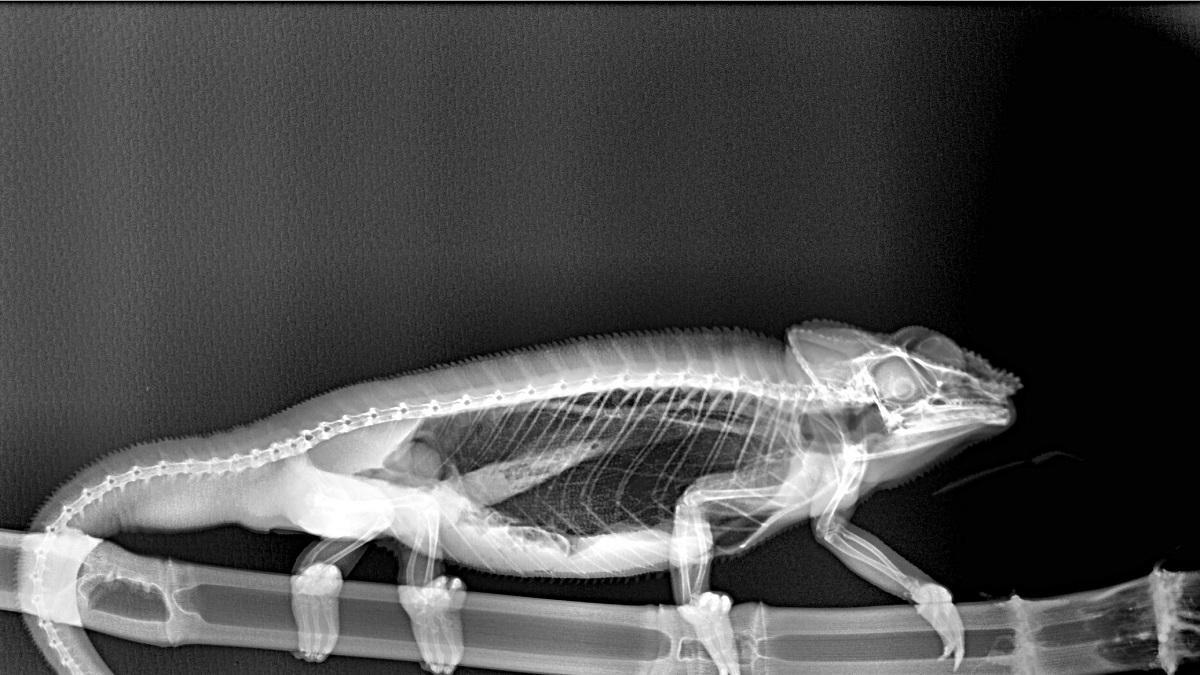

Radiografia de un camaleón. / L. O.

Cada uno de los animales que alberga Bioparc Fuengirola recibe numerosas atenciones que garantizan su bienestar y aseguran que su estado de salud sea el correcto. Entre estos trabajos, se encuentran los seguimientos médicos que realiza el equipo de Veterinaria del parque. Unos controles que, por supuesto, incluyen radiografías.

Este procedimiento diagnóstico permite a estos expertos brindar una excelente atención médica. Al exponerlos a los rayos X, el equipo puede tomar fotografías de las partes óseas internas de los animales, comprobando la existencia de lesiones o enfermedades que a simple vista no podrían ser identificadas.

Radiografía de un camaleón de Biopark Fuengirola. / L. O.